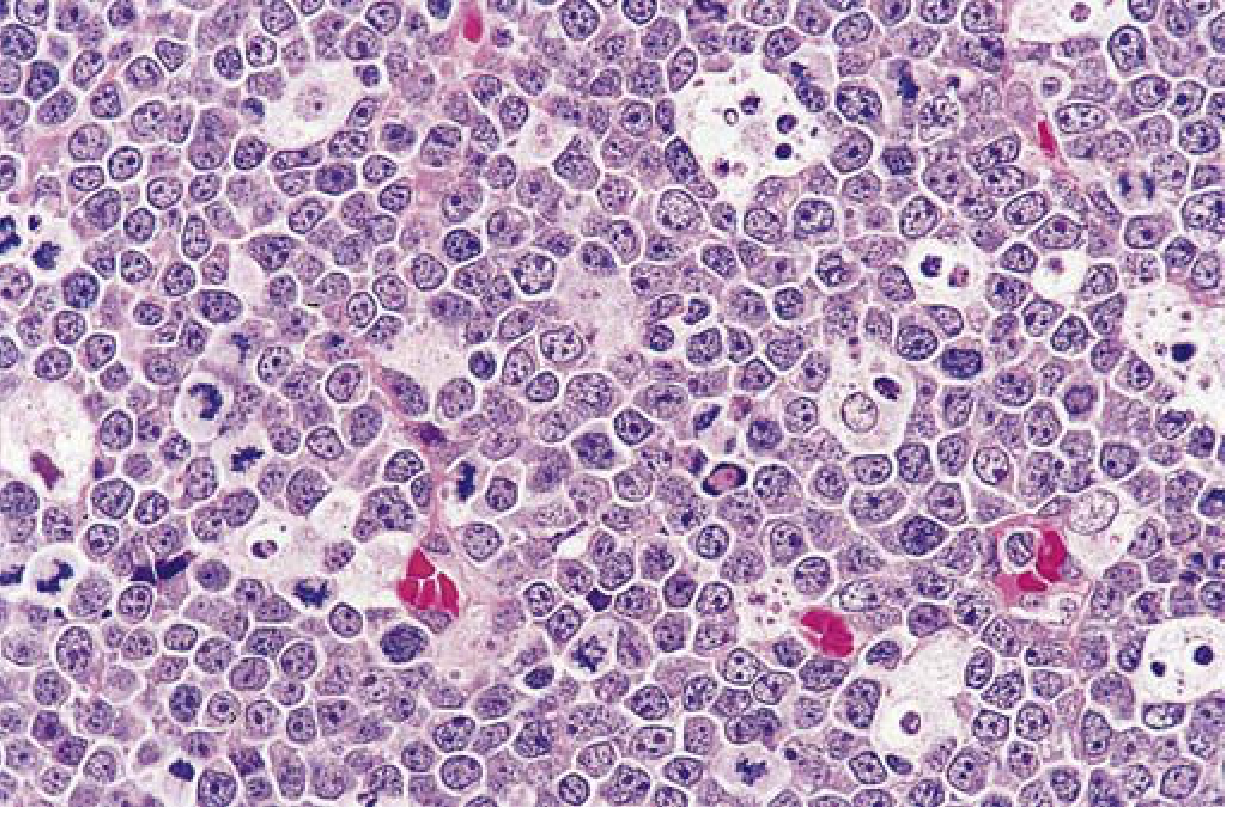

H&E bone marrow trephine biopsy showing diffuse infiltration by plasma cells in multiple myeloma

H&E bone marrow biopsy — sheets of malignant plasma cells replacing normal marrow architecture.

Bone marrow:

• Plasma cells typically >30% of marrow cellularity (required for diagnosis)

• Cells may resemble normal plasma cells or show abnormal features:

• Prominent nucleoli

• Russell bodies — cytoplasmic inclusions containing immunoglobulin (Fig. 10.28B)

• Late disease: spread to viscera and soft tissues; terminal stage may show a leukemic picture